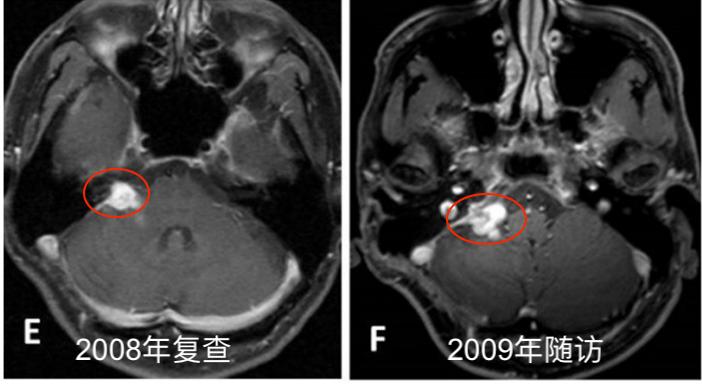

E. 2008年5月随访的轴位钆剂(Gd)增强T1加权MR图像。F.2009年11月随访的轴位钆剂(Gd)增强T1加权MR图像。

2004年5月,采取右侧乙状窦后入路切除肿瘤。术中肿瘤质地坚实(solid),血管相对丰富,易出血,部分切除肿瘤(图1A-B),于2005年8月行伽玛刀放射外科治疗(GKS)(图2)以控制当时的残留肿留。2007年5月行第二次手术切除,因蛛网膜边缘不清,与面听神经和后组颅神经粘连严重,残留部分肿瘤囊壁(图1C-D)。病人每6个月定期随访脑部MRI(图1E-I),最初的残留肿瘤的大小是稳定的。2013年11月,常规随访MRI显示肿瘤开始生长(图1J)。2014年4月出现进行性头痛、眩晕、和恶心,MRI显示肿瘤肿块增大。2014年6月(图1K-L)进行次全肿瘤切除,术中发现显示,肿瘤有两个部分,也就是说,有一部分是软的且相对容易切除,另一部分有弹性伴有纤维组织,蛛网膜边界不清楚,与面听神经和后组颅神经严重粘连。本病例的第二次及第三次手术均由同一位神经外科医生完成。